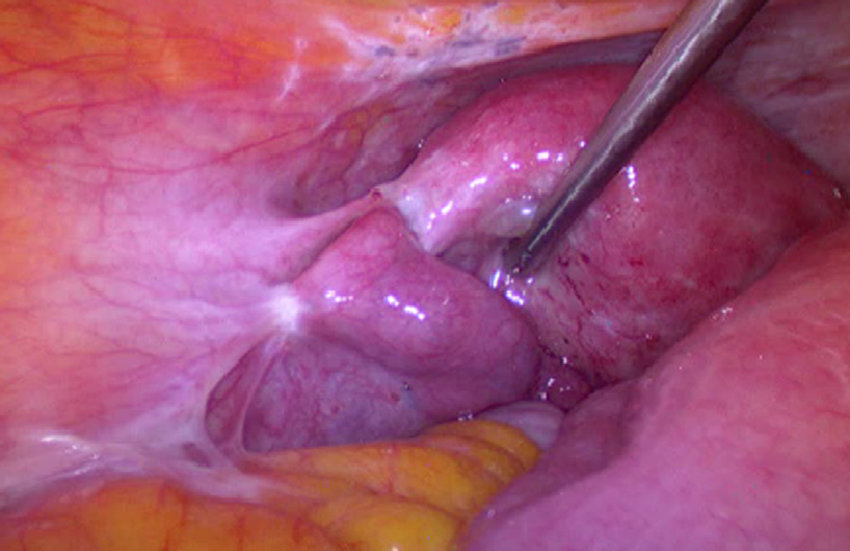

اندومتریوز معمولا با لاپاراسکوپی تایید می شود. این یک عمل کوچک است که شامل ایجاد یک برش کوچک، تحت بیهوشی، در دیواره شکم (شکم) زیر دکمه شکم (ناف) است. یک ابزار نازک تلسکوپ مانند (لاپاروسکوپ) از طریق پوست فشار داده می شود تا به داخل آن نگاه کند. تکه های اندومتریوز توسط پزشک قابل مشاهده است.با این حال، علائم آندومتریوز می تواند ناشی از شرایط دیگر باشد. بنابراین، اگر هر یک از علائم آندومتریوز بالا ماندگار شد، معمولاً آزمایشاتی برای یافتن علت علائم توصیه می شود.

لاپاراسکوپی

این روش جراحی با بیهوشی عمومی انجام میشود. پزشک از طریق یک برش کوچک در شکم دوربین کوچکی را وارد میکند تا به طور مستقیم داخل لگن را مشاهده کرده و در صورت نیاز نمونهبرداری (بیوپسی) انجام دهد. لاپاراسکوپی دقیقترین روش برای تشخیص قطعی اندومتریوز است و به پزشک این امکان را میدهد که ضایعات اندومتریوز را شناسایی و درمان کند.

در برخی موارد، پزشک متخصص برای بررسی دقیقتر، بیمار را برای انجام عمل لاپاراسکوپی به جراح ارجاع میدهد. لاپاراسکوپی نوعی جراحی کمتهاجمی است که با بیهوشی عمومی انجام میشود. طی این روش، برشی کوچک در نزدیکی ناف ایجاد شده و ابزاری باریک و بلند با دوربین کوچکی به نام لاپاراسکوپ وارد حفره شکمی میشود. پزشک از طریق این دوربین میتواند داخل شکم را مشاهده کرده و نشانههای وجود بافتهای اندومتریوز را بررسی کند. همچنین امکان برداشت نمونههای بافتی برای آزمایشهای بیشتر فراهم میشود. اطلاعاتی مانند محل دقیق، میزان گسترش و اندازه ضایعات با این روش بهدست میآید.

گاهی اوقات جراحی برای برداشتن برخی از تکه های بزرگتر اندومتریوز توصیه می شود. اگر مشکل ناباروری باشد، عمل ممکن است علائم را کاهش دهد و احتمال بارداری را افزایش دهد.تکنیک های مختلفی وجود دارد که می توان از آنها استفاده کرد. معمولاً یک ابزار نازک تلسکوپ مانند (لاپاروسکوپ) از طریق یک بریدگی کوچک در شکم (شکم) رانده می شود. سپس جراح از لاپاراسکوپ برای دیدن داخل شکم و برداشتن کیست ها یا سایر بافت های اندومتریوز (جراحی سوراخ کلید) استفاده می کند.

نحوه تشخیص آندومتریوز

بسیاری از افراد مبتلا به اندومتریوز بر اساس علائم خود بدون تشخیص رسمی درمان می شوند. در موارد دیگر، تشخیص رسمی از طریق لاپاراسکوپی، یک جراحی ساده انجام می شود. در این روش، پزشکان یک برش کوچک در شکم ایجاد میکنند (معمولاً زیر 1.5 سانتیمتر/0.6 اینچ) و دوربینی را برای مشاهده داخل حفره لگن وارد میکنند. نمونههای بافت کوچک ممکن است جمعآوری شوند که بیوپسی نامیده میشوند.

لاپاراسکوپی

بیشتر آندومتریوز باید با دیدن آن به طور دقیق و مستقیم تشخیص داده شود. این بدان معناست که بیماران باید حداقل یک نوع جراحی جزئی به نام لاپاراسکوپی انجام دهند.

در این عمل یک برش کوچک در ناف ایجاد می شود و سپس یک تلسکوپ به داخل حفره شکم وارد می شود تا تمام اندام ها و سطوح لگن را به دقت بررسی کند. به این ترتیب می توان اندومتریوز را به درستی شناسایی کرد و شدت آن را ارزیابی کرد.